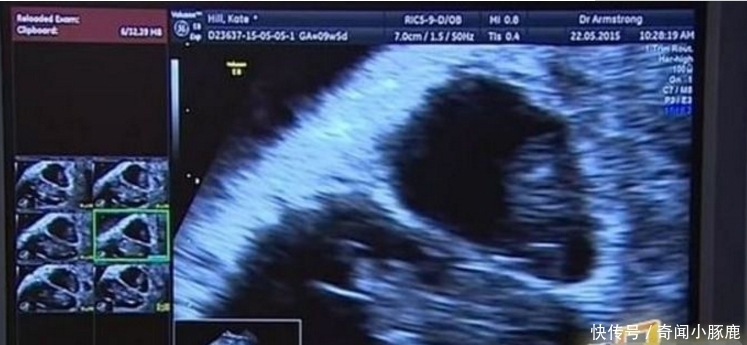

然而就在妻子怀孕3个月后到医院做产检却被医生告知她再次怀孕,这一个消息可把女子惊到了。明明刚怀孕三个月第一个孩子还未出世怎么会又再次怀孕呢?

原来医生检查后发现,女子患有比较罕见的子宫畸形,导致女子即使怀孕了依然有卵子排出,最终导致了女子再次怀孕。医生说这种现象十分罕见,女子现在所怀的两个孩子并不能称之为真正意义上的双胞胎,因为这两个孩子的诞生是一前一后。